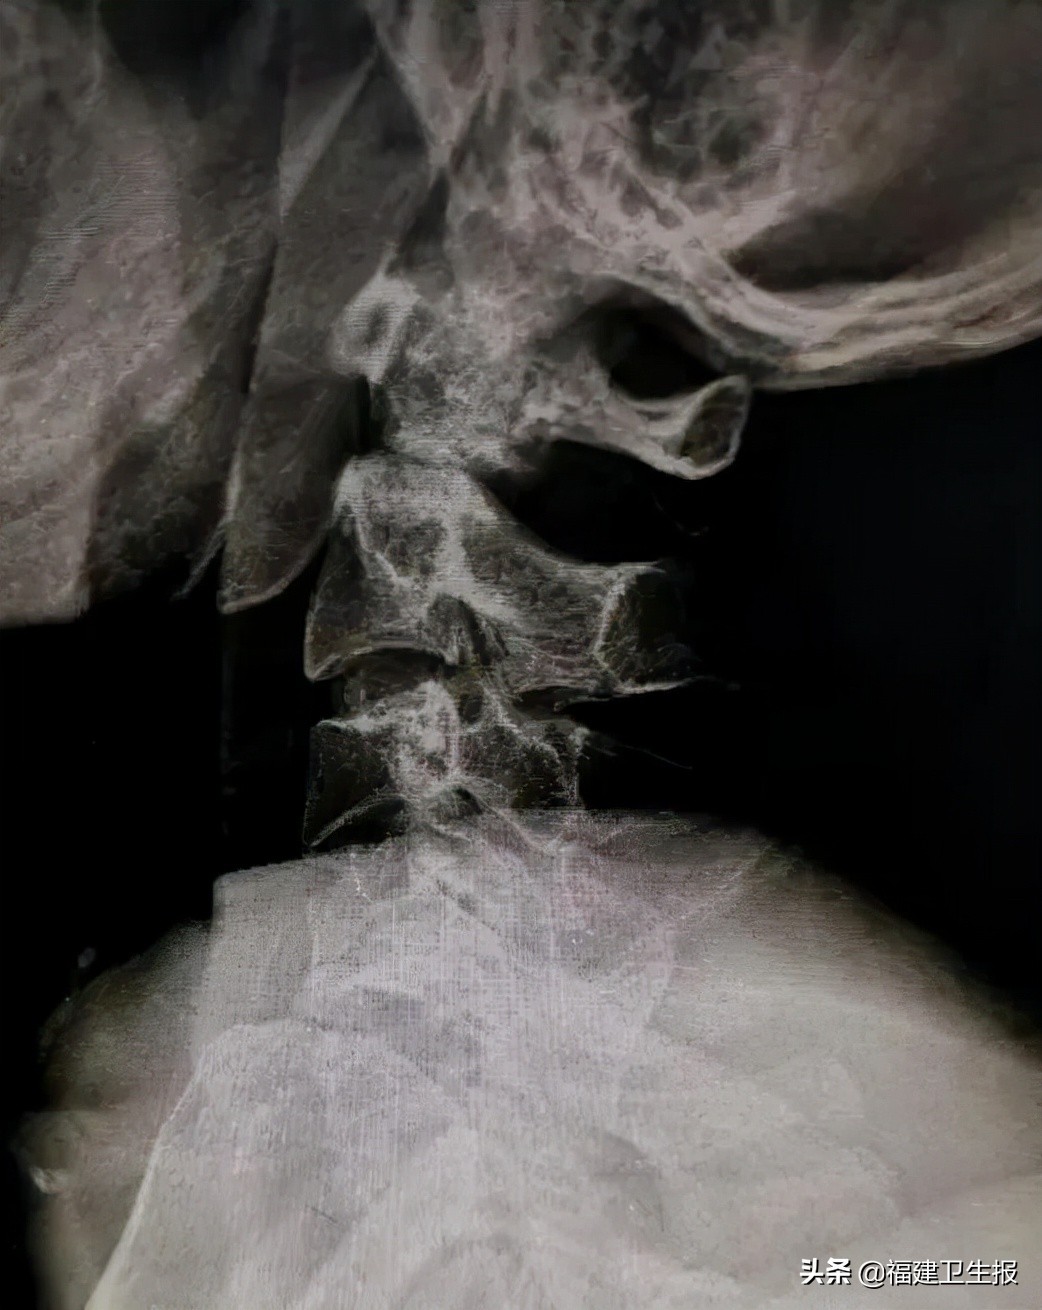

50岁的刘某因不慎摔伤致颈部疼痛、颈部活动受限,并有双侧上肢无力、麻木,就诊于福建医科大学附属第一医院泉港总医院。急诊颈椎CT检查报告为枢椎齿状突骨折伴寰椎椎体后脱位。

▲患者术前X光